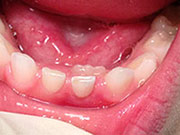

Adult Teeth Coming in Behind Baby Teeth

This is a very common occurrence with children, usually the result of a lower,

primary (baby) tooth not falling out when the permanent tooth is coming in. In most

cases if the child starts wiggling the baby tooth, it will usually fall out on its own

within two months. If it doesn't, then contact your pediatric dentist, where they can

easily remove the tooth. The permanent tooth should then slide into the proper place.